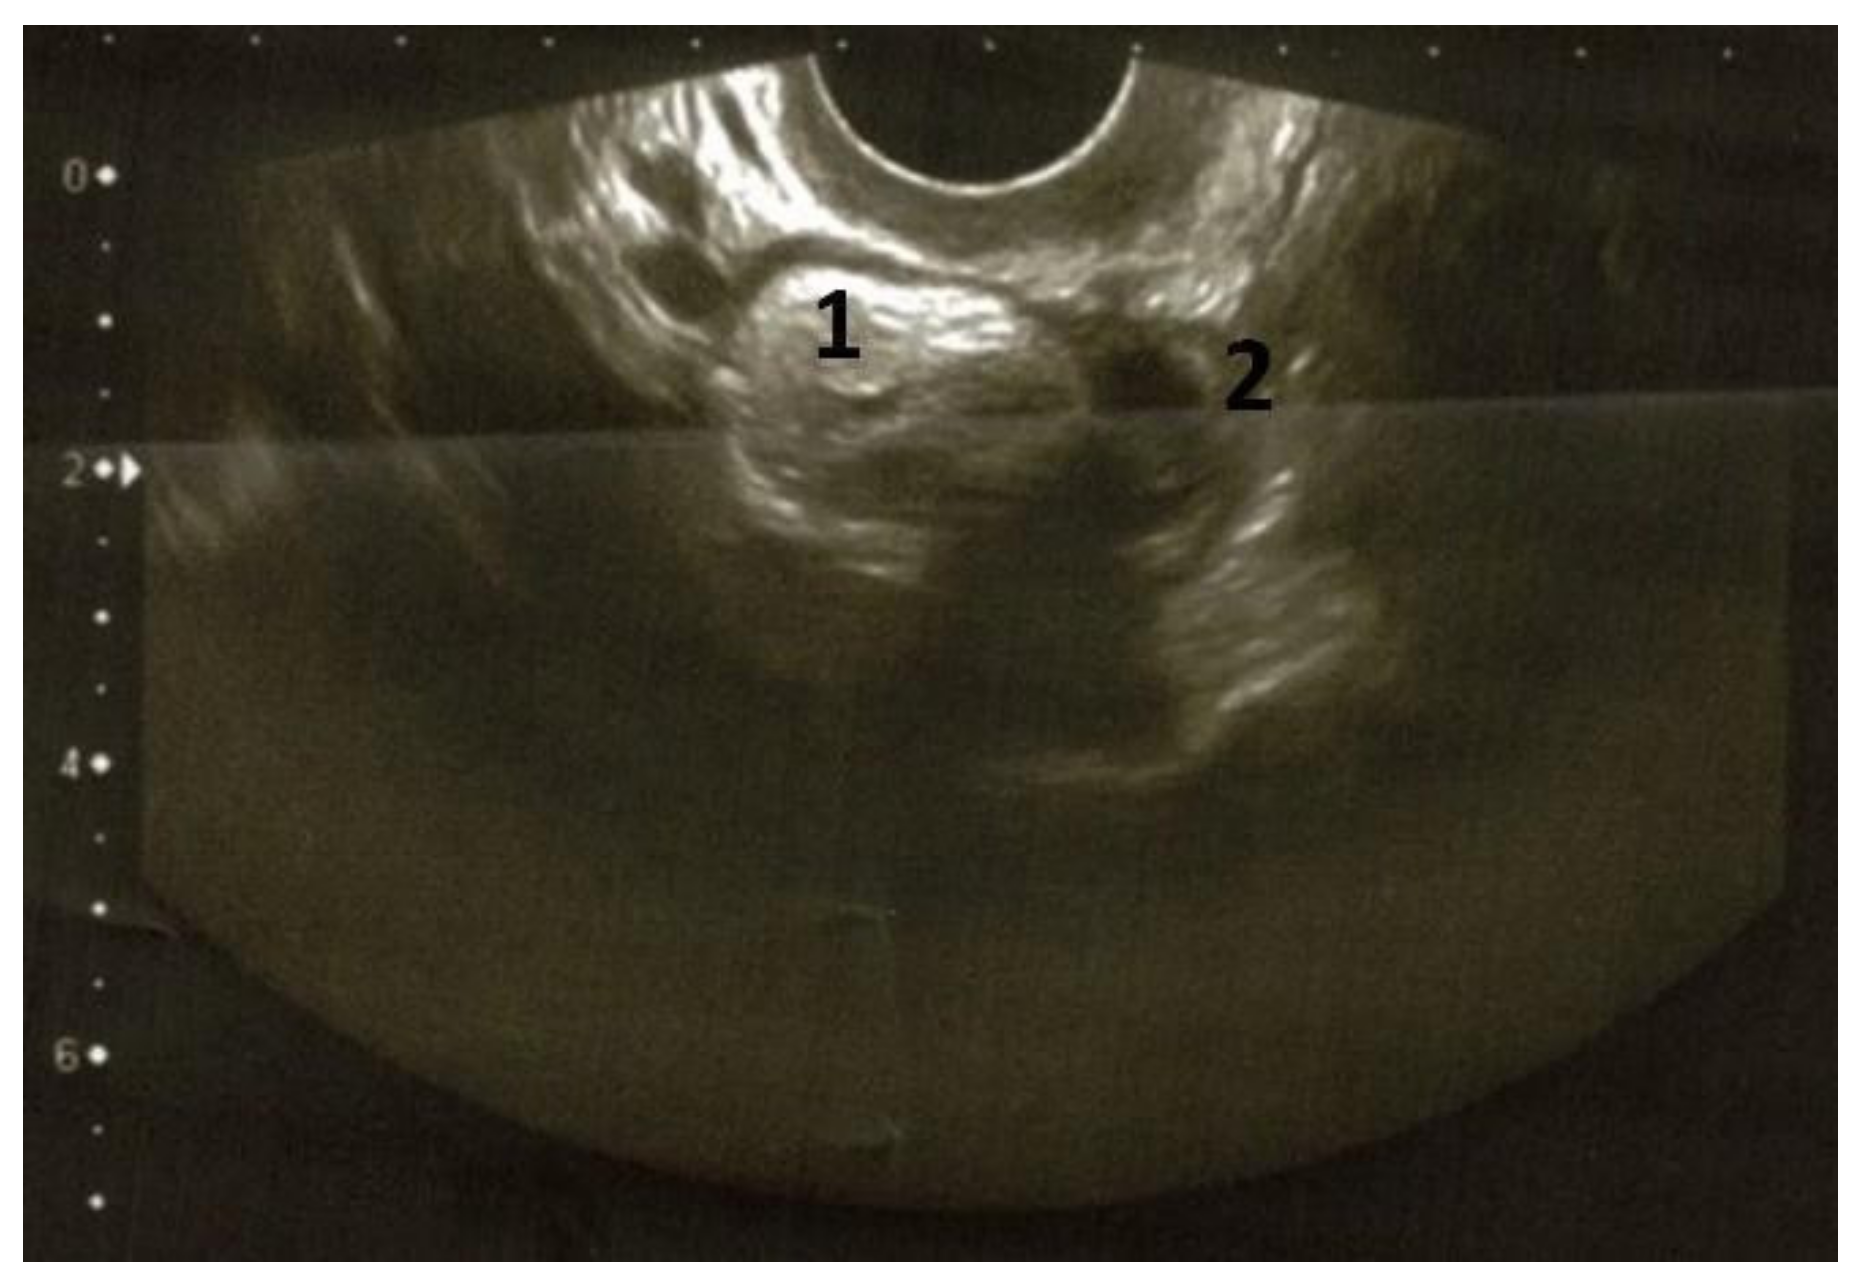

The preoperative pelvic US scans demonstrated a left ovarian, solid mass of 3.5 × 3.4 × 3.0 cm; the tumor was hyperechoic and showed clear smooth contours without vascularization zones (Figure 3).

Figure 3. Transvaginal ultrasound examination (2020) of the left ovarian teratoma. The left ovary showed a solid tumor (3.5 × 3.0 × 3.4 cm) with increased echogenicity and clear smooth contour, without vascularization zones (1: tumor; 2: remaining ovarian tissue; previously unpublished, original photos).